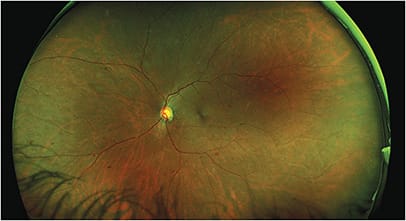

This SLO image shows severe non-proliferative retinopathy with multiple microaneurysms and intraretinal hemorrhages, cotton-wool spots, and exudates. Image taken from Heidelberg Engineering SPECTRALIS OCT.